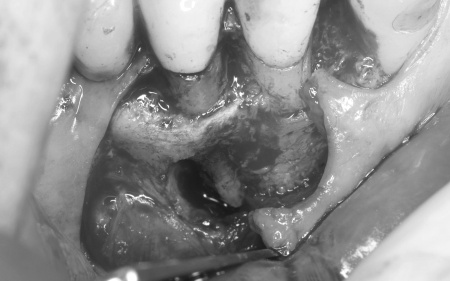

| 診断 | 拝見したところ、右下の奥歯周辺の歯ぐきが腫れていました。

歯やあごの骨の状態を詳しく調べるためレントゲン検査を行った結果、右下の奥歯2本(第2小臼歯、第1大臼歯)は、歯根が縦方向に割れている可能性が高いと考えられました。 しかし、レントゲン画像だけでは歯根の状態を正確に判断することはできません。 歯根が割れている場合、細菌感染が進行して歯ぐきの炎症が広がったり周囲の歯やあごの骨にまで影響を及ぼしたりする可能性があります。 以上のことから、歯を温存することは難しいため抜歯が必要と診断しました。 |

治療前

歯根破折が疑われました。